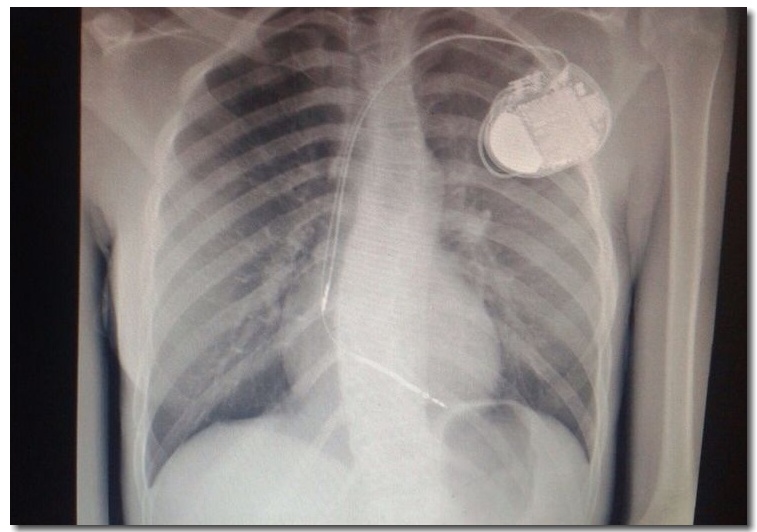

El procedimiento para implantar este dispositivo es muy similar al que se realiza para insertar un marcapasos. “La intervención se realizó bajo anestesia general, tuvo una duración de una hora aproximadamente y consistió en hacer dos pequeñas punciones en el pecho de la paciente, justo por debajo de la clavícula izquierda, para desde allí mediante Rayos X, avanzar dos electrodos a través de las venas hasta llegar a las cavidades derechas del corazón para ‘anclarlos’ (uno en la punta del corazón y el otro en la aurícula derecha), y luego conectar las otras puntas de los cables al cardiodesfibrilador ubicado en el pecho de la paciente”.

Posteriormente se realizaron los estudios electrofisiológicos para verificar el correcto funcionamiento del dispositivo y concluyó exitosamente el procedimiento. “Según el protocolo médico, la paciente fue trasladada por 24 horas a la unidad de cuidados intensivos para realizar monitoreo permanente, radiografía de tórax, electrocardiograma y se verificó la estabilidad hemodinámica de la paciente”, dijo el cirujano.